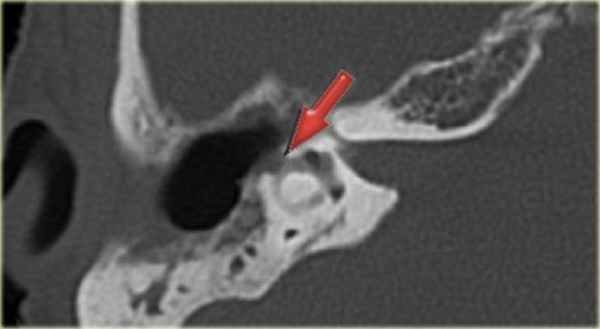

КТ-картина дефекта латерального полукружного канала (фистула)

вследствие холестеатомы у 53-летней пациентки с клиникой головокружения